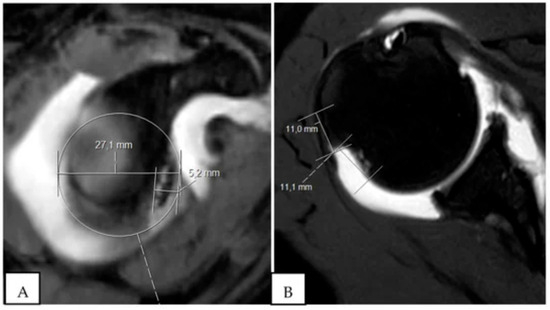

Figure 5. Best-fit-circle method of measuring glenoid bone loss. D = Diameter of best-fit circle, W = Width of defect, W/D = % of bone loss.